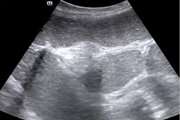

بررسی ارزش تشخیصی(حساسیت و ویژگی) یافته های سی تی اسکن مولتی اسلایس با تاکید بر کلترالهای مختلف در کشف واریس مری و احتمال خونریزی واریسی در بیماران مبتلا به سیروز کبدی مراجعه کننده به بیمارستان امام خمینی تهران بین سال ۹۲ تا ۹۸ 1404/01/17 - 10:54